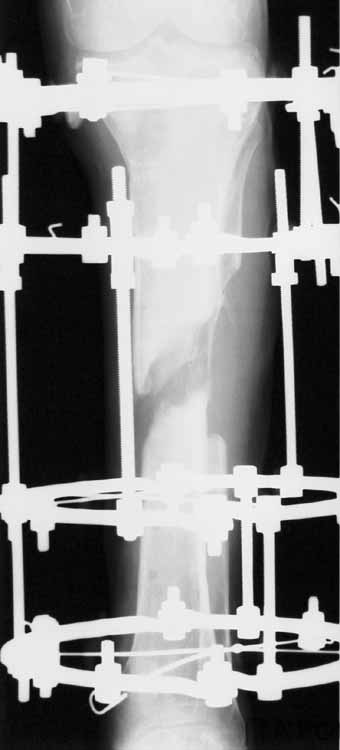

Ввиду относительной тугоподвижности ложного сустава и наличия признаков репаративной активности костной ткани рентгенологически, после 10 дней компрессии на стыке отломков, начали дистракцию по 1мм в день. Выписан на амбулаторное лечение. Отделяемое в нижней трети голени прекратилось, ранка закрылась. Интраоперационно и 5 дней после операции получал ципроксациллин. В июле по передней поверхности голени в зоне регенерата открылась ранка с обильным гнойным отделяемым. После локального лечения, ранка в течении двух недель эпителизировалась и полностью закрылась. Дистракцию не прекращали. (during 1, 2)

10 дней назад ранка на передней поверхности средней трети голени и по внутренней поверхности нижней трети голени, (по проекции стержня апп.Гофмана) открылись вновь. В настоящий момент отделяемого из обеих ран нет (wound1;2).